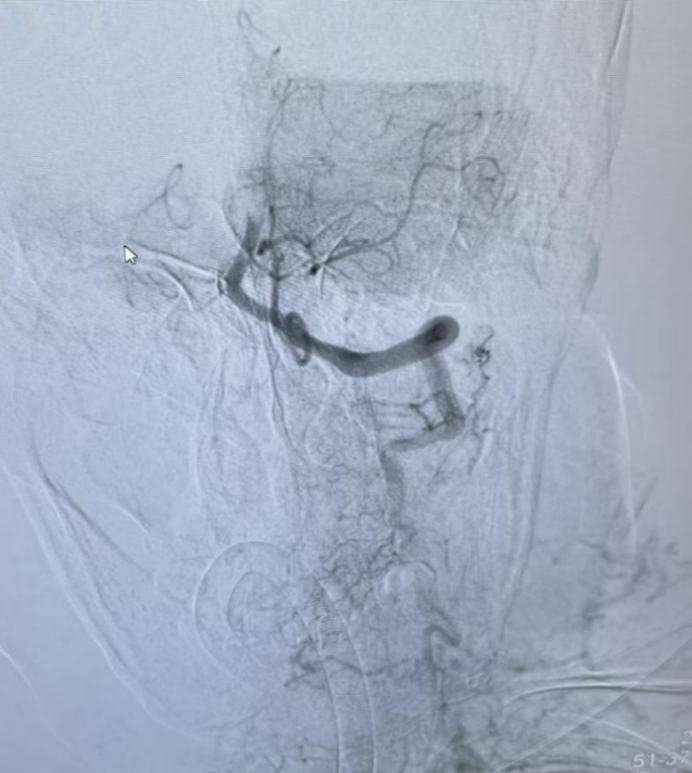

介入团队随即接力上阵,在全麻下进行脑血管造影,清晰显示基底动脉末端闭塞,远端未见明显显影。

造影显示

血管再通良好!

介入手术后血管完全再通